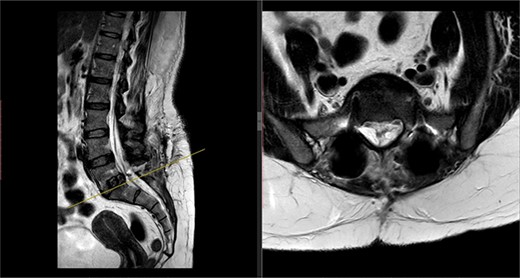

A repeat MRI scan (Fig. 2) performed in December 2016 did not show any interval changes as compared to the scan performed in February 2016. The patient presented elsewhere and was recommended for spinal fusion surgery. A posterior pedicle screw instrumentation with rods and a posterior interbody cage procedure was performed elsewhere in January 2017.

Preoperative MRI of the lumbar spine performed in December 2016. The MRI shows no neurological compression.